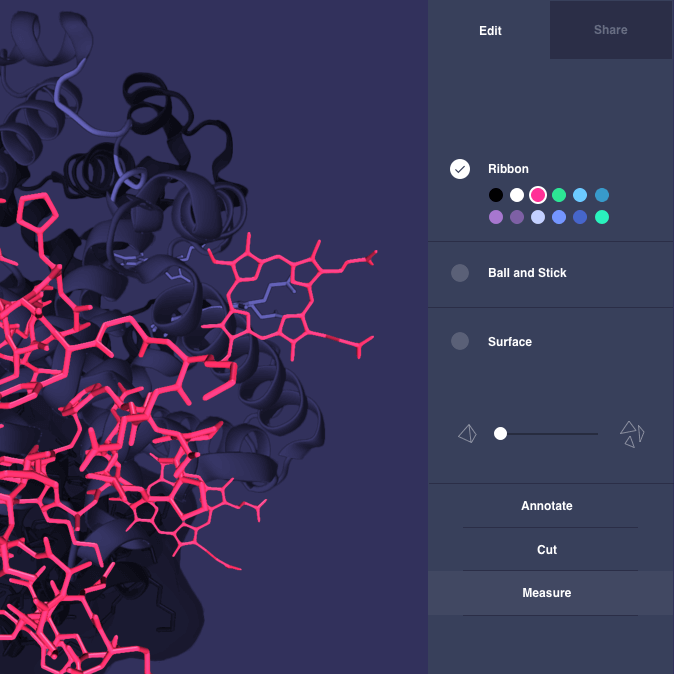

Application

Design System

First Experience

Application